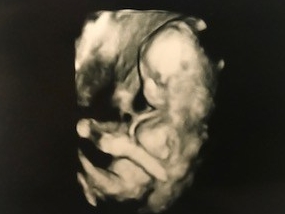

Right: 3D picture of baby girl…

FINDING OUT THE SEX: We had it scheduled to find out the sex somewhere around twenty weeks. Although, we went into an appointment to see my doctor around eighteen weeks and we walked into the big room set up with ultrasound equipment. She had me lay down to look at the baby’s heartbeat and make sure everything looked good. My husband and I asked, “Is there anyway you can tell if it is a boy or a girl?” We expected her to answer our question, but she surprised us with her response. She knew that we were anxious to know the sex… but instead of answering our question with a ‘yes’ or a ‘no’, she replied, “It’s a GIRL!” There was no warning or build up… I quickly looked over at my husband’s face and we were shocked and excited! I had a gut feeling I was having a girl, but I never expected it to be true because of our family. I have three brothers, my mother has one brother, my dad has three brothers, and I have four nephews… this is going to be one spoiled little baby girl!